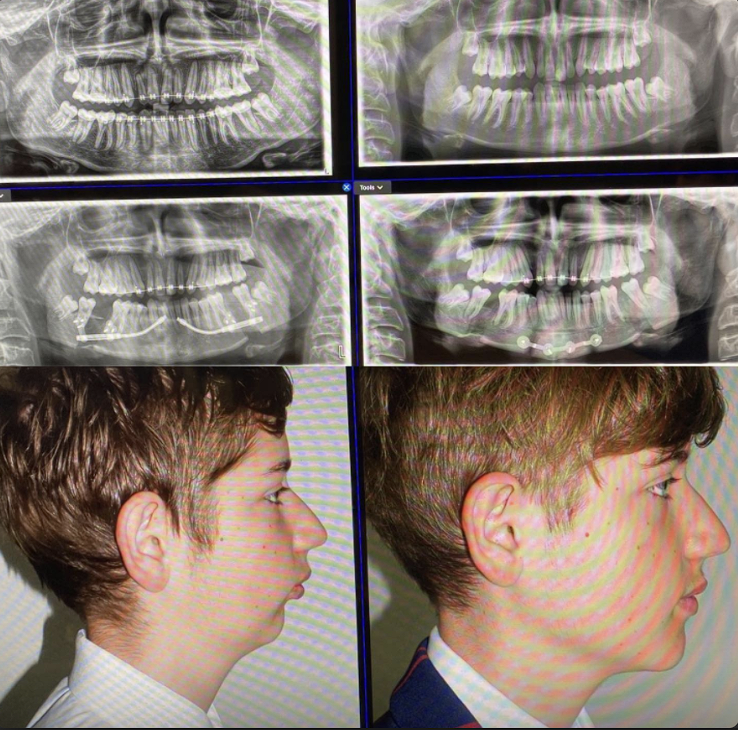

↓↓Tam olarak emin olmamakla birlikte before/after↓↓

4- Mandibular Advancement via Distraction Osteogenesis

Bu yöntem, mandibulanın tek seferde değil, kademeli olarak ileri alınması için kullanılır. Kemik kesilir ve distraktör ile günler–haftalar boyunca yavaş yavaş açılır. Amaç ani gerilim yerine kontrollü kemik uzamasıdır.

Distraction osteogenesis genelde ileri derecede mandibular gerilik olan vakalarda tercih edilir. Tek seferde yapılacak BSSO’nun riskli olacağı veya yetersiz kalacağı durumlarda kullanılır.

Estetik kazanç vardır ama süreç uzundur. Taşınan sadece kemik değil, yumuşak dokudur; bu yüzden sonuçlar genelde stabil olur. Ancak cihaz süreci ve hasta uyumu kritik faktördür.

Attentionspancels: Distraction, hafif vakalar için değil; büyük mandibular ilerleme gereken durumlar içindir. Daha zor, daha uzun ama doğru vakada etkilidir.

UYARI!!!: Bu genellikle çocuklar için yapılan bir uygulamadır.

↓↓Before/After↓↓

↓↓Tam olarak emin olmamakla birlikte before/after↓↓

4- Mandibular Advancement via Distraction Osteogenesis

Bu yöntem, mandibulanın tek seferde değil, kademeli olarak ileri alınması için kullanılır. Kemik kesilir ve distraktör ile günler–haftalar boyunca yavaş yavaş açılır. Amaç ani gerilim yerine kontrollü kemik uzamasıdır.

Distraction osteogenesis genelde ileri derecede mandibular gerilik olan vakalarda tercih edilir. Tek seferde yapılacak BSSO’nun riskli olacağı veya yetersiz kalacağı durumlarda kullanılır.

Estetik kazanç vardır ama süreç uzundur. Taşınan sadece kemik değil, yumuşak dokudur; bu yüzden sonuçlar genelde stabil olur. Ancak cihaz süreci ve hasta uyumu kritik faktördür.

Attentionspancels: Distraction, hafif vakalar için değil; büyük mandibular ilerleme gereken durumlar içindir. Daha zor, daha uzun ama doğru vakada etkilidir.

UYARI!!!: Bu genellikle çocuklar için yapılan bir uygulamadır.

↓↓Before/After↓↓